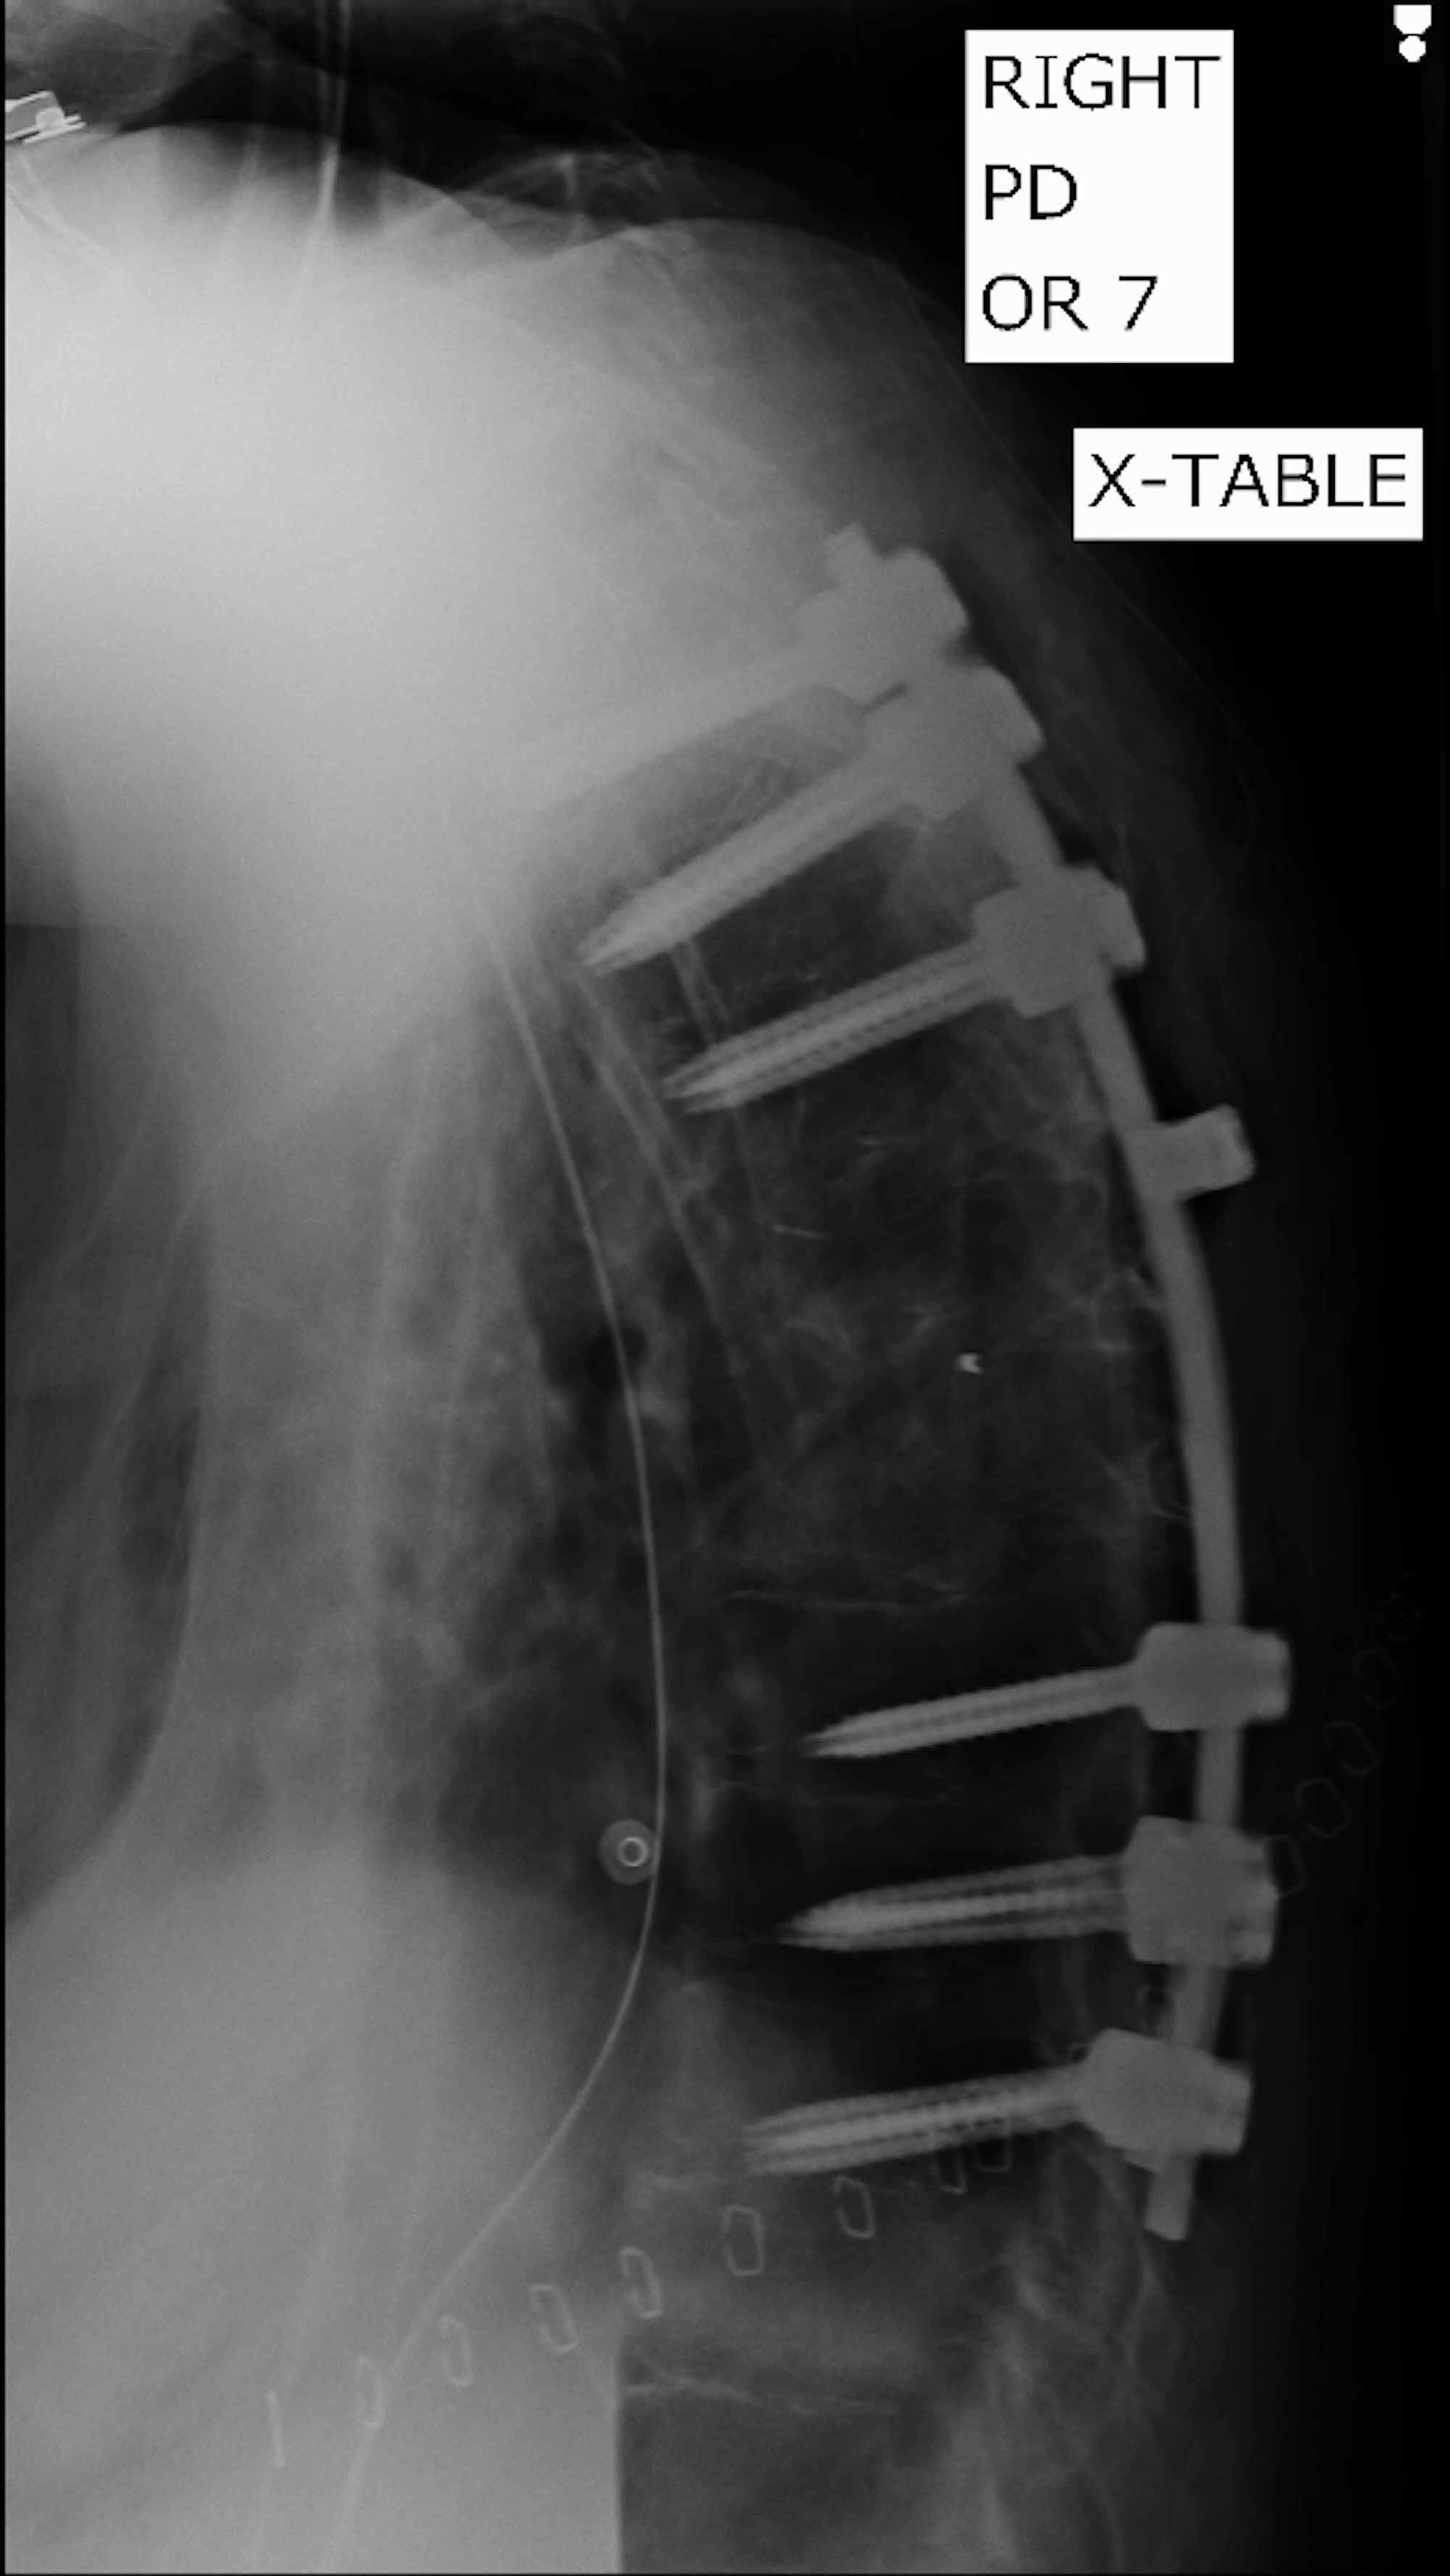

(PDF) Pott's Disease Medical and surgical treatment Pott's Disease Recurrence Pott’s disease (spinal tuberculosis) is a bacterial infection that affects the bones in your spine. Tb disseminates to the vertebral column, it is called pott’s disease or spinal tb. Malnutrition, nonstandard chemotherapy, nonradical debridement,. It was described as early as 1000 to 600 bce as yakshama in ancient indian medical literature as. Tuberculosis (tb), as a disease has been known. Pott's Disease Recurrence.